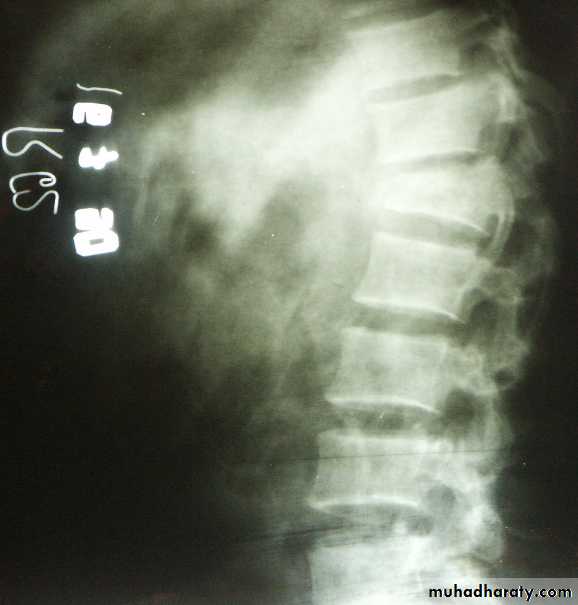

1.TOMOGRAPHY: In spine or tibia condyle injure.2. CT, MRI: In spine fracture which threatened the cord.